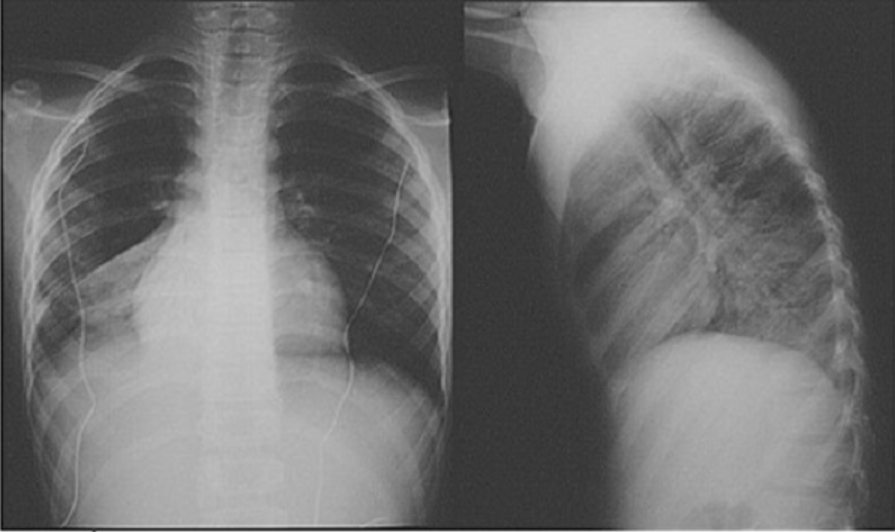

Người bệnh sẽ được tiến hành chụp phim X quang tim phổi để theo dõi hình dạng hai phổi và chức năng hô hấp.